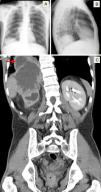

Un varón de 45 años de edad ingresó en el servicio de neumología por presentar tos, expectoración, hemoptisis y dolor torácico pleurítico en el costado derecho de 2 semanas de evolución. El paciente refería anorexia, pérdida de unos 6kg de peso y sudoración nocturna profusa en los 2 meses anteriores. Durante algunos meses había presentado episodios de disuria, polaquiuria, nicturia y dolor lumbar bilateral que se irradiaba a las ingles. La exploración física mostró una ligera disminución de los tonos respiratorios en la base del pulmón derecho y dolor leve a la palpación profunda del flanco abdominal derecho. La radiología de tórax (fig. 1) reveló una opacidad redondeada en la base pulmonar derecha, y la TAC toracoabdominal (fig. 1) confirmó la presencia de una gran masa abdominal que invadía el tórax (véase la leyenda de la figura). El examen anatomopatológico de la lesión reveló un carcinoma escasamente diferenciado de aparente origen endotelial urológico. Se inició quimioterapia, pero el paciente falleció unos 8 meses más tarde debido a la progresión de la enfermedad.

A y B) Imágenes radiológicas torácicas (posteroanterior y lateral, respectivamente) que revelan una opacidad redondeada en la base del pulmón derecho. C) TAC toracoabdominal (plano coronal) que muestra una gran masa abdominal de unos 13×11×8,3cm, aparentemente originada en el riñón derecho, que invade el lóbulo hepático derecho, el diafragma y el lóbulo inferior del pulmón derecho (ver la flecha en el campo superior izquierdo).